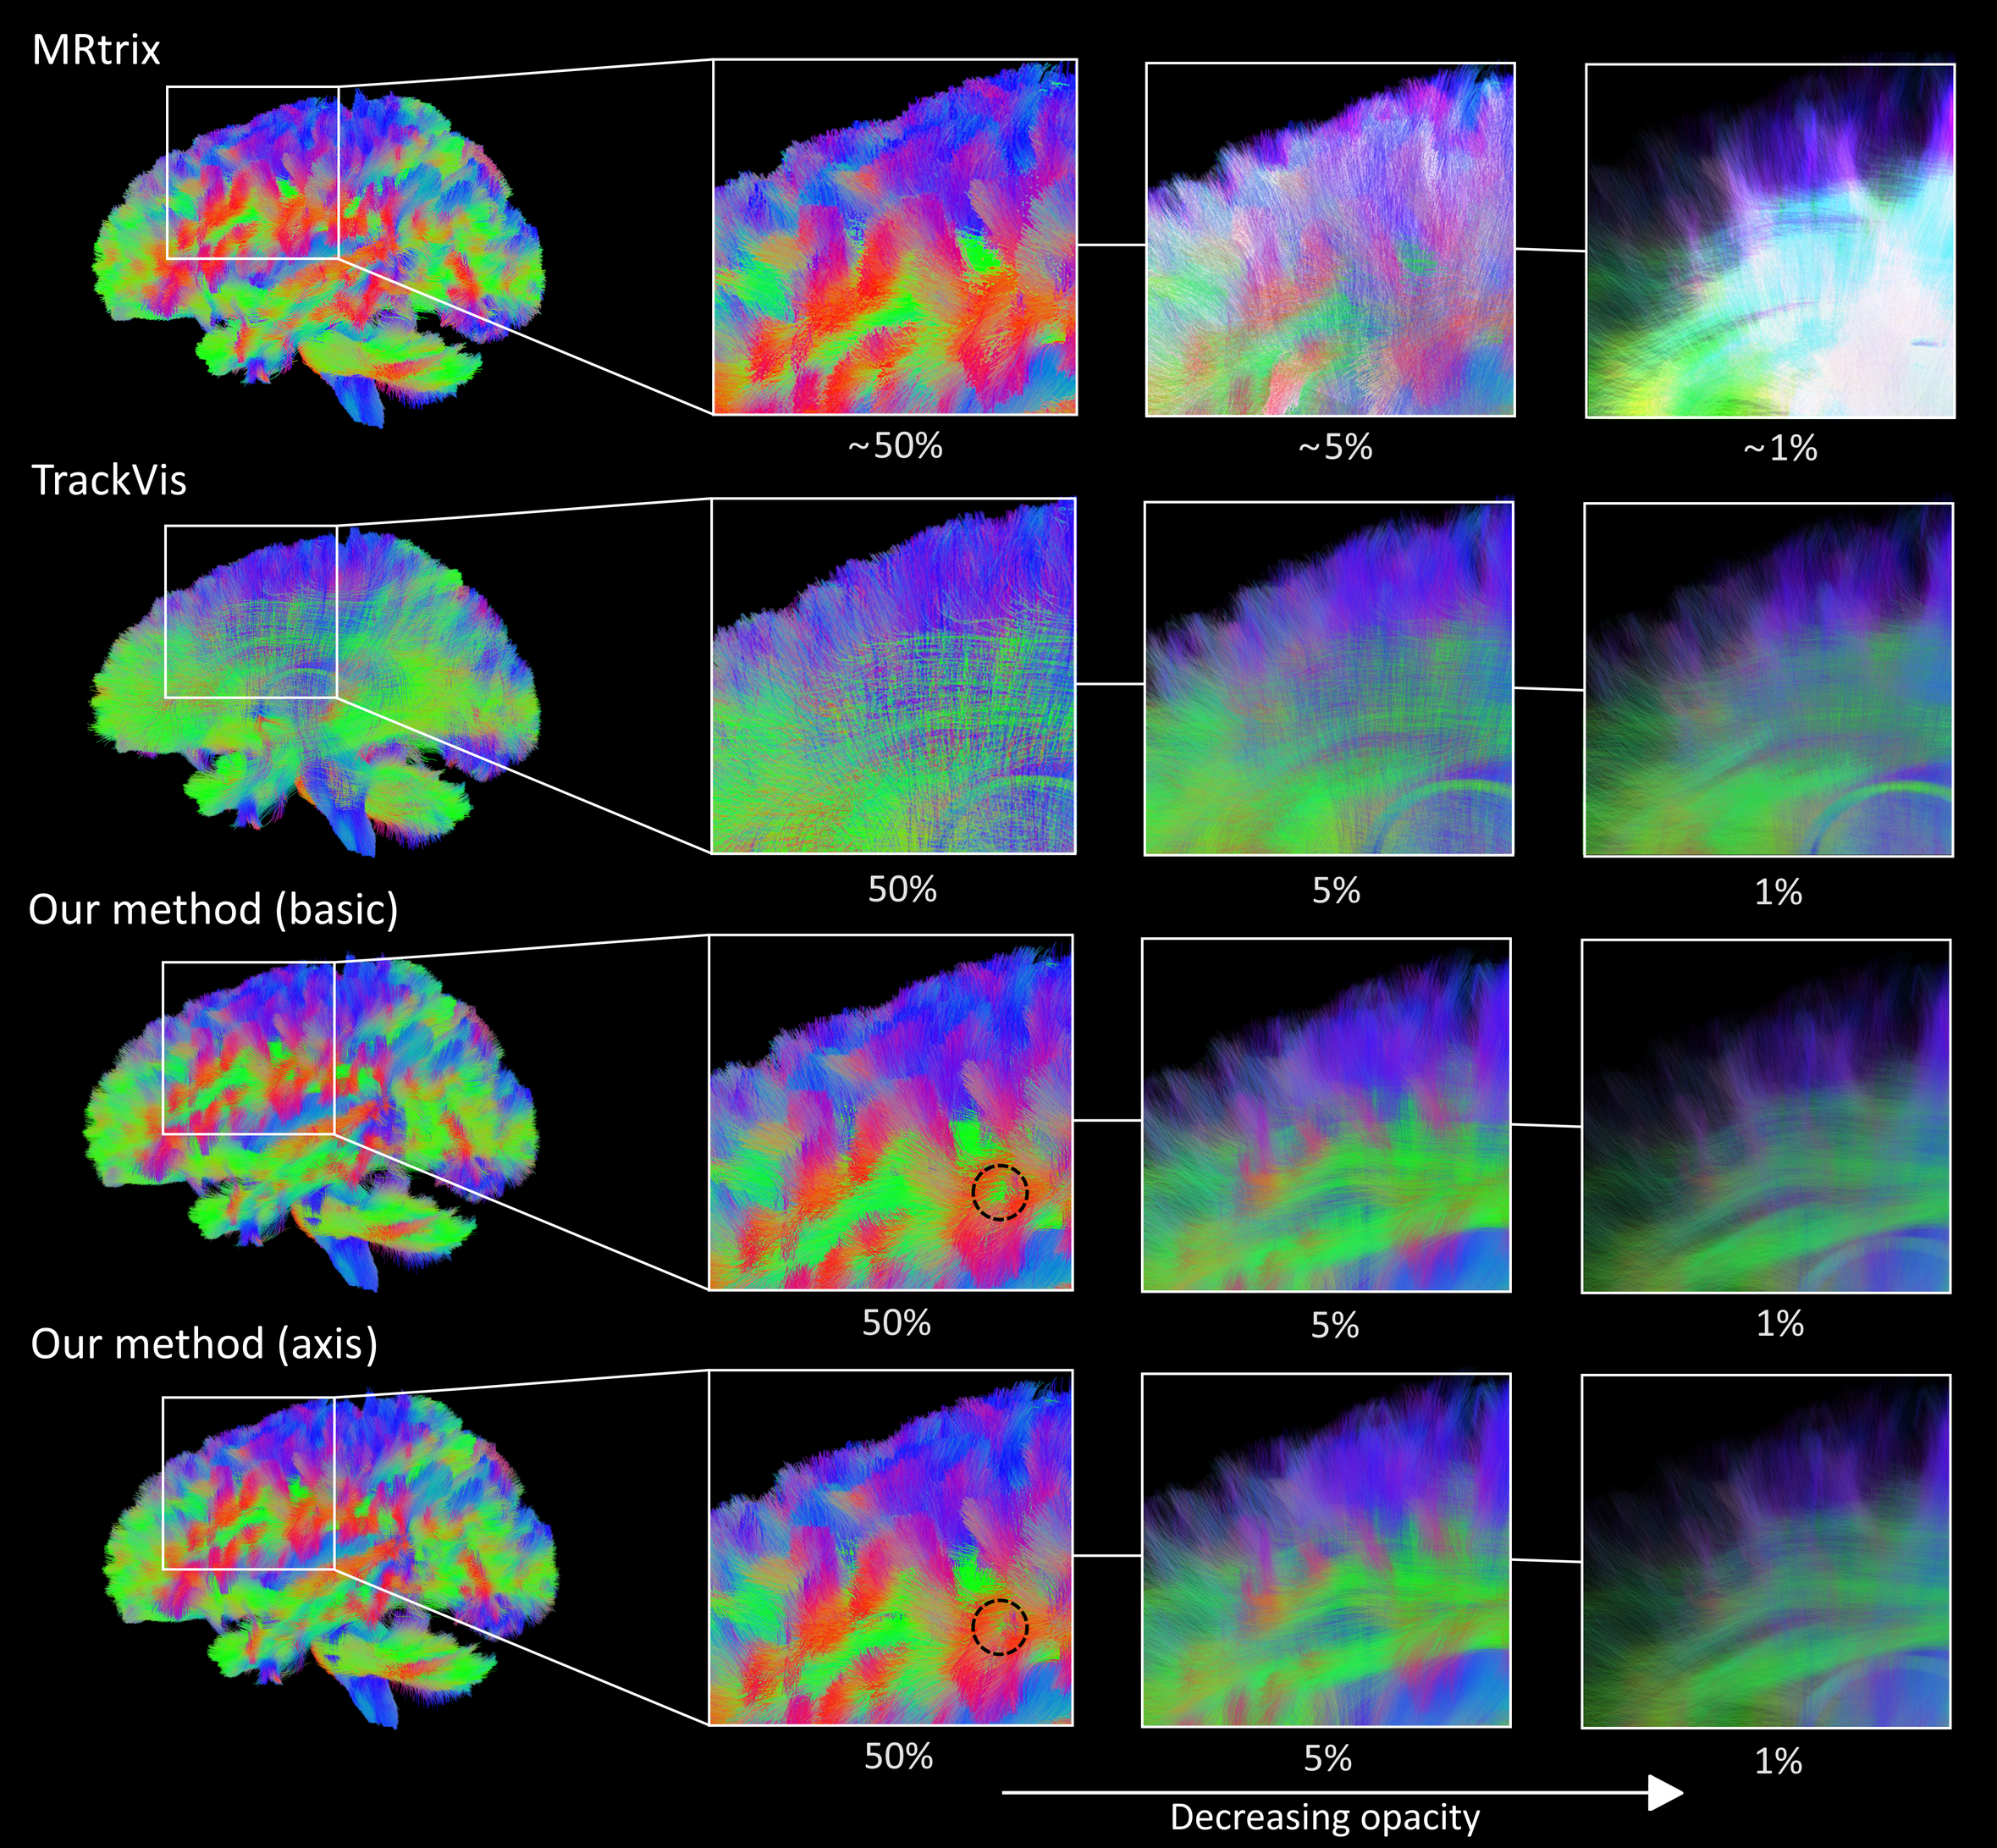

Figure 3 displays different transparency values for each method using a single dataset. MRTrix handles transparency by blending two renders of the dataset, one with a depth buffer and another without, based on the transparency value of the dataset [4]. While this approach preserves line render order, it makes it challenging to visualize the internal structures of the dataset. TrackVis renders transparent streamlines based on the given dataset, causing noticeable render order issues, particularly when streamline transparency is low.

In our method, by utilizing only voxelization (basic), we can observe more information about the streamlines deeper in the brain with minimal sorting inaccuracy. This is evident in the figure, for example, green superior longitudinal fasciculus fibers can be seen behind the red, short superficial fibers . Increasing transparency increases the visibility of the superior longitudinal fasciculus fibers without distorting the fact that the short superficial fibers are in front, while MRTrix and TrackVis have more difficulty conveying this information.

When applying axis sorting, the render order issues are slightly reduced. Although it may be challenging to discern in the image, axis method gives a more accurate representation of the render order compared to basic method. For instance comparing highlighted regions in Figure 3 shows axis sorting bringing out certain red superficial fibers in front more clearly compared to the method without axis sorting.